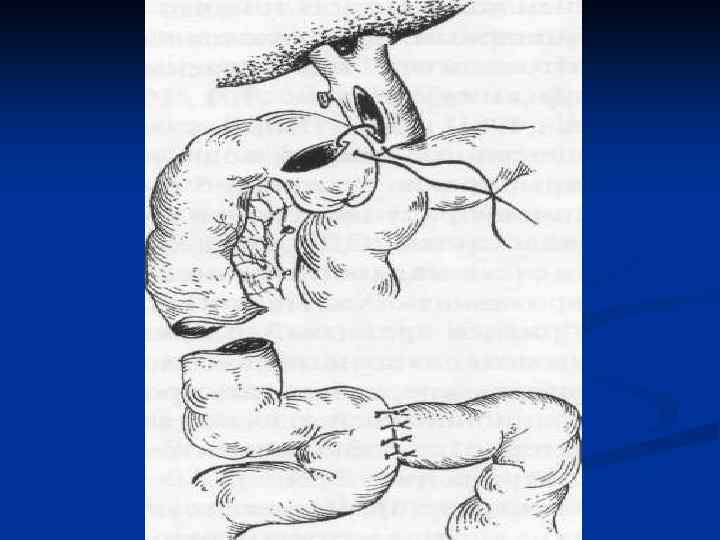

I. Восстановительные операции (восстановление проходимости протоков) 1. Эндобилиарные вмешательства под УЗИ или R – контролем (бужирование, баллонная дилатация, стентирование протоков). 2. Пластика стриктуры 3. Иссечение стриктуры с наложением анастомоза. II. Реконструктивные операции (наложение билиодигестивных анастомозов) 1. Анастомозы внепеченочных желчных протоков: а) с двенадцатиперстной кишкой (ХДА) б) с тощей кишкой (гепатико-, холедохоеюноанастомозы по Ру или по Брауну). 2. Анастомозы внутрипеченочных желчных протоков с сегментом тощей кишки, выключенной по Ру или желудком при высоких стриктурах

I. Восстановительные операции (восстановление проходимости протоков) 1. Эндобилиарные вмешательства под УЗИ или R – контролем (бужирование, баллонная дилатация, стентирование протоков). 2. Пластика стриктуры 3. Иссечение стриктуры с наложением анастомоза. II. Реконструктивные операции (наложение билиодигестивных анастомозов) 1. Анастомозы внепеченочных желчных протоков: а) с двенадцатиперстной кишкой (ХДА) б) с тощей кишкой (гепатико-, холедохоеюноанастомозы по Ру или по Брауну). 2. Анастомозы внутрипеченочных желчных протоков с сегментом тощей кишки, выключенной по Ру или желудком при высоких стриктурах